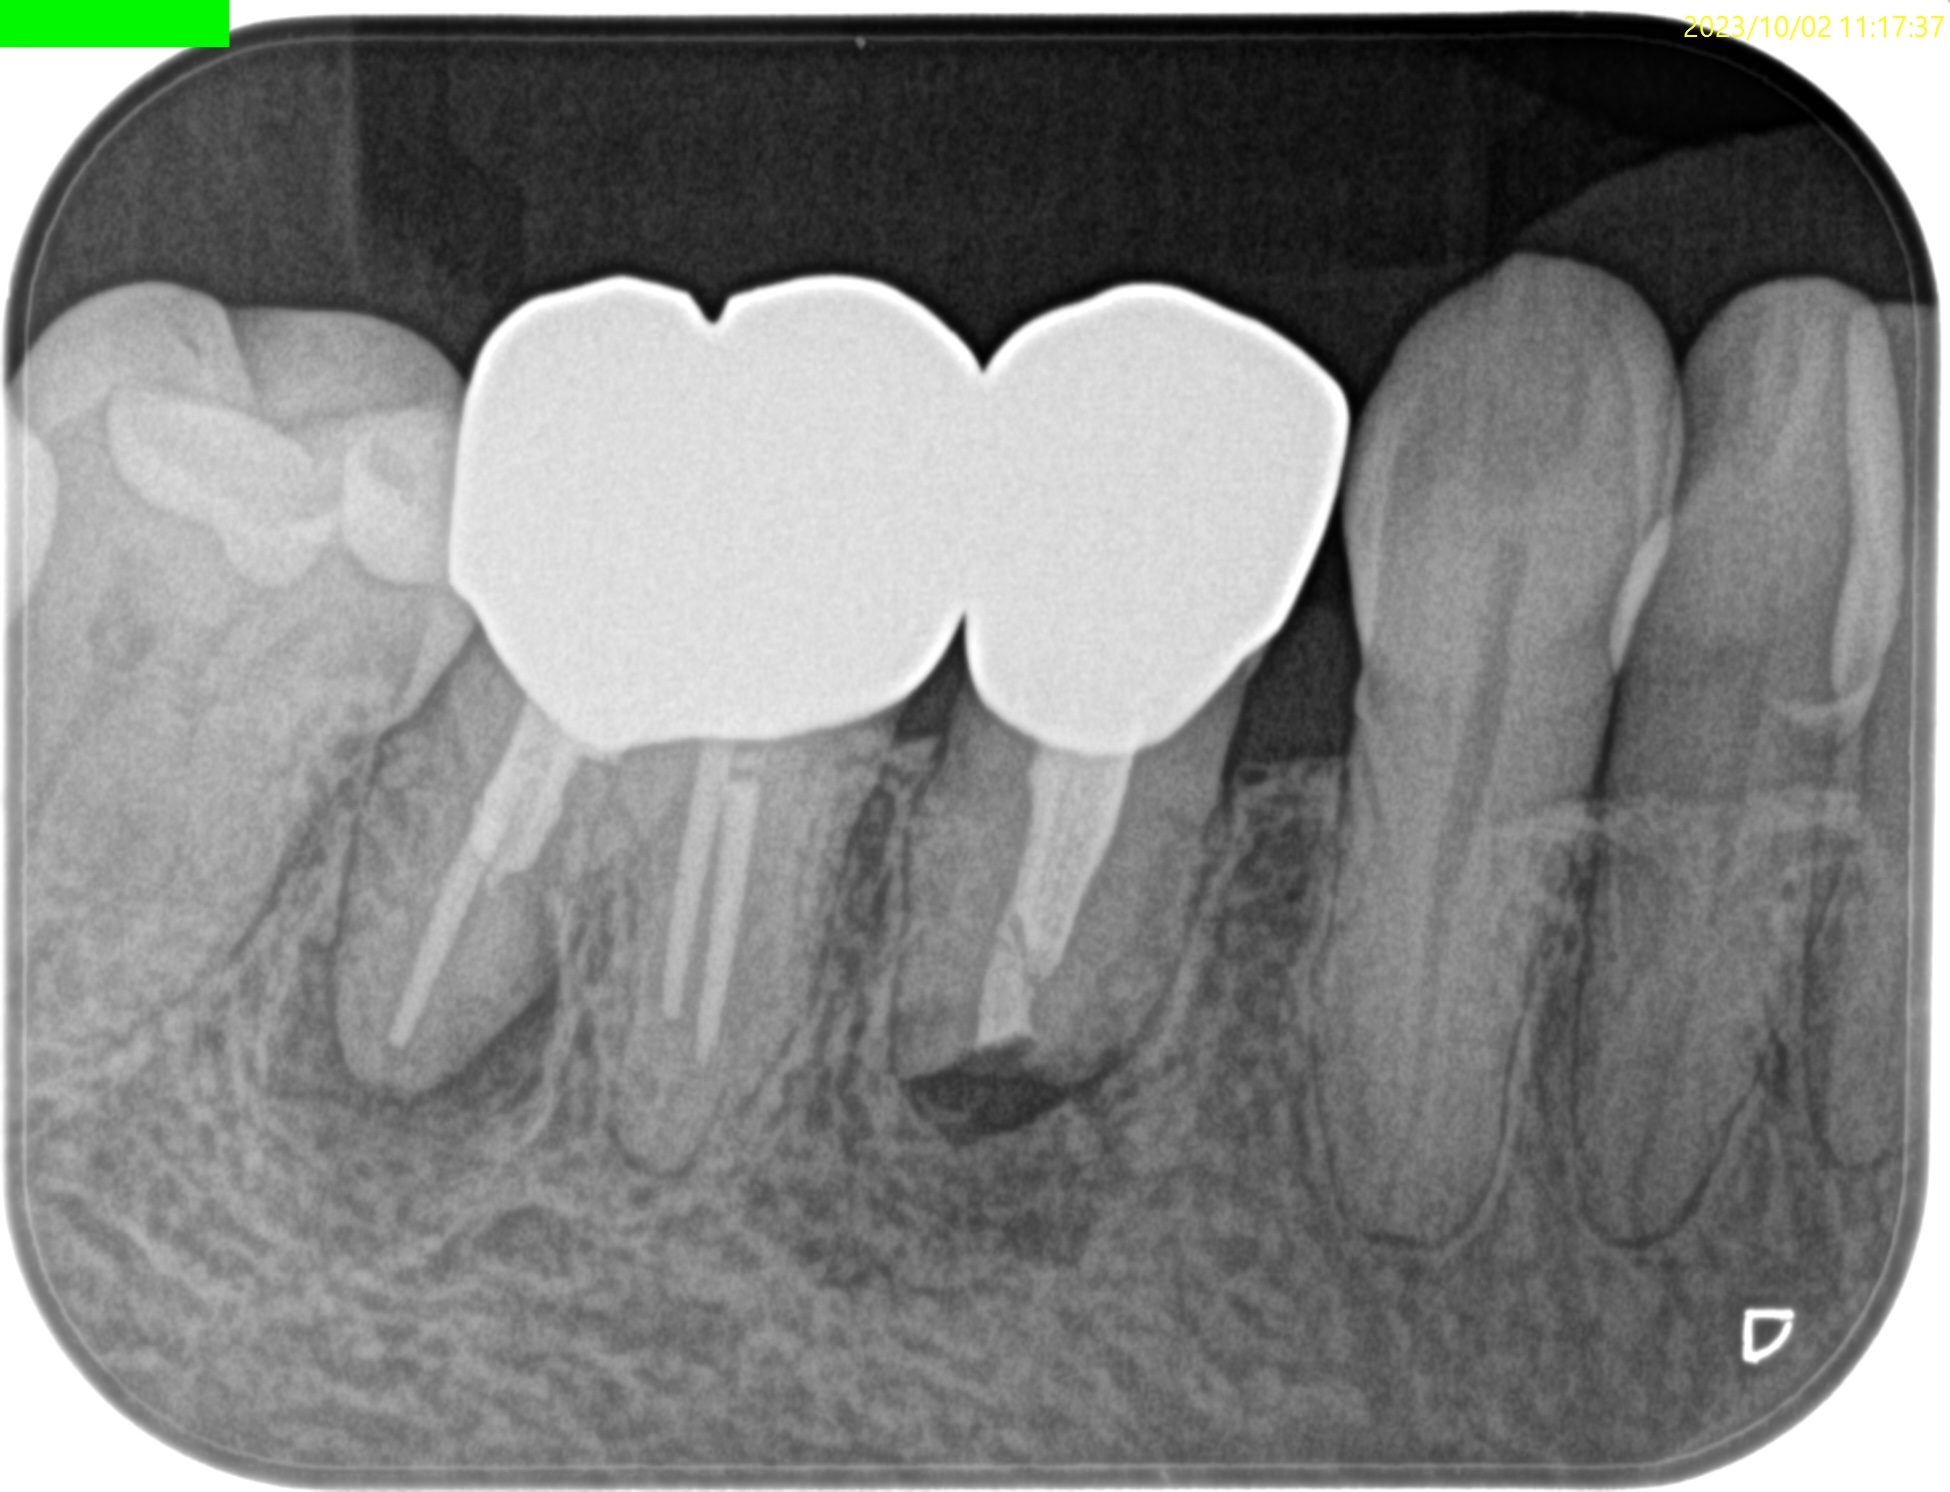

1年後にFinalが装着された。

病変が治癒していない。

3年経過したのに、だ。